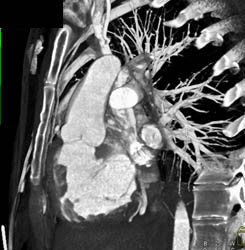

Diagnosis

Normal LAD